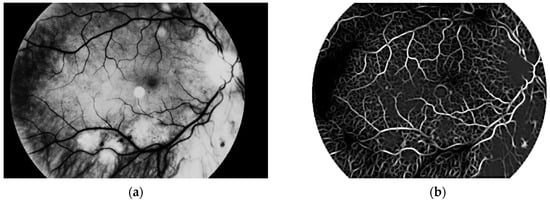

Another step, noise removal, is also done with median filtering. This algorithm is an efficient way to get precise results. Original image and images obtained after both of these steps are presented in Figure 10.

The third and the fourth steps are connected with image enhancement before vessel segmentation. It is done on the basis of histogram equalization (which allows enhancement of the image contrast) and brightness correction. Images obtained after both of these stages are presented in Figure 11.

Figure 10. (a) Original image, (b) image after conversion to grayscale with green channel and (c) image after noise removal.

Figure 11. Image after (a) histogram equalization and (b) after brightness correction.